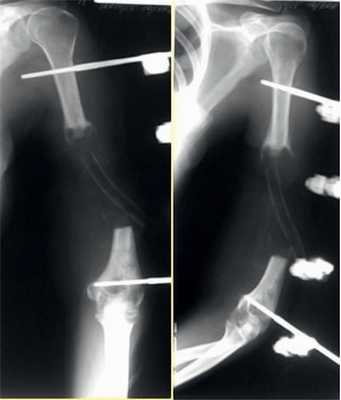

Рис. 7. Оперативное лечение пациентки И.: пластика левой плечевой кости свободным кровоснабжаемым трансплантатом из малоберцовой кости.

Клинический пример 2

Пациентка Н., 41 года.

Диагноз: ложный сустав левой плечевой кости.

На рис. 10-14 Рис. 10. Рентгенограмма пациентки Н. до операции. Рис. 14. Внешний вид и функция пациентки Н. через 8 мес после операции. представлены этапы обследования и лечения пациентки Н.

Рис. 11. Пациентка Н. Оперативное лечение: резекция зоны ложного сустава левой плечевой кости, остеосинтез пластиной и винтами. Пластика свободным кровоснабжаемым трансплантатом из внутреннего мыщелка бедренной кости.